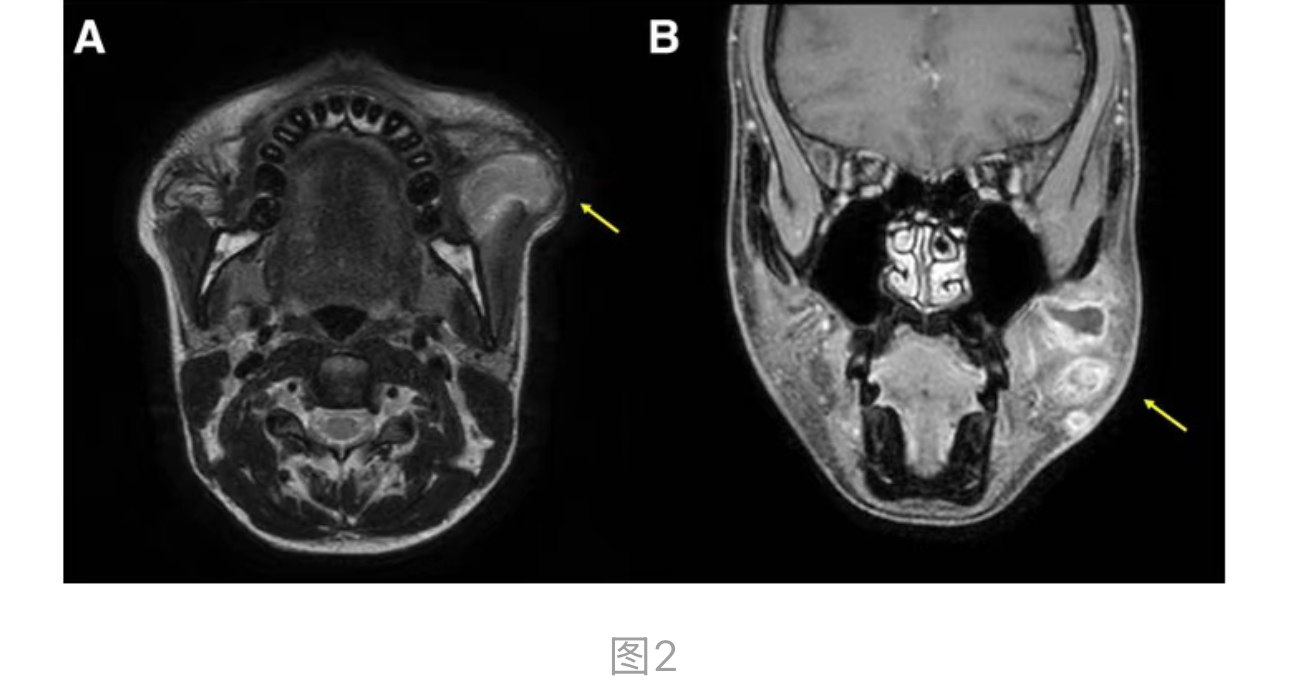

显示左颊有一个浸润性T2高信号病变,累及咬肌,伴有提示脂肪坏死和液体积聚的边缘强化(图 2. MRI 显示 SMAS 下层(sub-SMAS)有一浸润性 T2 高信号病变(黄色箭头),延伸至咬肌内。(A)轴位观 (B)冠状位观。MRI = 磁共振成像,SMAS = 表浅肌肉腱膜系统。)。该病变似乎延伸至表浅肌肉腱膜系统下层。给予了抗生素和抗炎药物,但症状无改善。因此,进行了手术干预,主要原因是肿胀的进行性以及不典型MRI发现带来的诊断不确定性,这需要通过组织病理学评估来最终排除肿瘤。